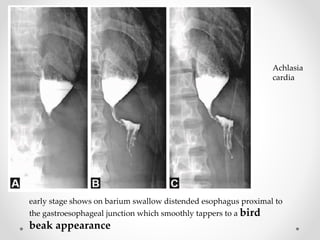

Achlasia

cardia

early stage shows on barium swallow distended esophagus proximal to

the gastroesophageal junction which smoothly tappers to a bird

beak appearance